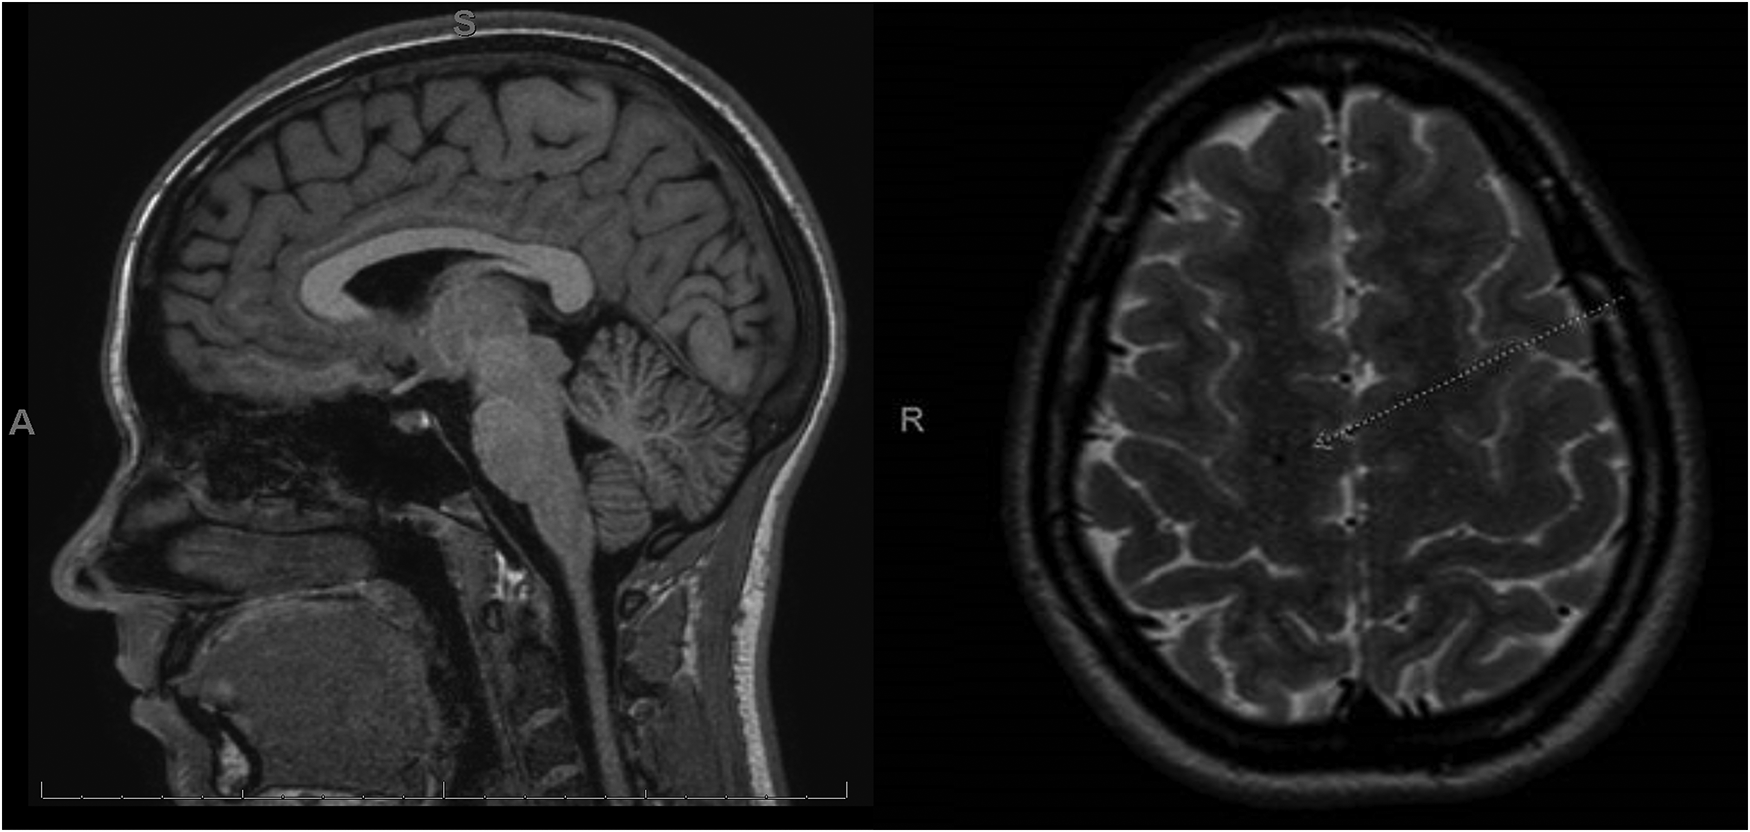

The patient is a competitive dancer and was accidentally kicked in the face during a routine, which resulted in a facial injury, bloody nose, dizziness, and headache. Immediately after the accident, the patient felt confused and disoriented with a headache that brought her to the emergency department. A maxillofacial CT revealed a left maxillary sinus fracture and minimally displaced nasal bone fracture, which did not require surgical intervention. One-week post-facial injury, the patient reported trouble sleeping, nausea, constant frontal headaches without relief from medications, dizziness sit-to-stand, dizziness while walking, trouble focusing, increased light sensitivity and blurred vision with difficulty tracking, and increased fatigue, thus requiring a neurology consult. During the consult, the patient displayed left-sided upper and lower extremity weakness and difficulty with balance testing, displaying a mild truncal sway and stepping off midline repeatedly with tandem gait forward, backward, and forward with eyes closed. A diagnosis of concussion was confirmed, and a brain MRI ordered, revealing no intracranial abnormality but showing an incidental right frontal developmental venous anomaly (Figure 2).

Figure 2

MRI post-concussive brain imaging of the patient. In this case, the patient received an MRI 2 weeks after injury. The MRI revealed an incidental right frontal developmental venous anomaly (white arrow) and was otherwise normal. No pre-concussive MRIs are available for comparison.